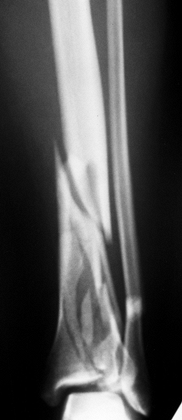

Grade II open, midshaft, slightly comminuted fracture of the left femoral shaft (Fig. 14.5). Figure 14.5. Fracture of the shaft of the left femur. Note that no fracture of the femoral neck can be seen. Figure 14.5. Fracture of the shaft of the left femur. Note that no fracture of the femoral neck can be seen.